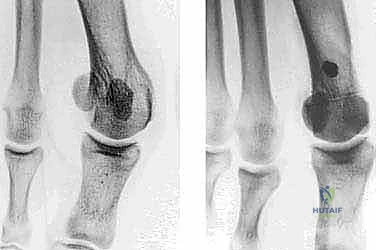

- التصوير بالأشعة السينية الدقيقة (Weight-Bearing X-Rays): وهي خطوة حاسمة. يجب أن تؤخذ الأشعة والمريض واقف (يحمل وزنه على قدمه) لإظهار الحجم الحقيقي للتشوه.

- القياسات الهندسية لزوايا القدم: يقوم الدكتور هطيف بقياس زوايا محددة لتحديد نوع الجراحة، أهمها:

- HVA (Hallux Valgus Angle): زاوية انحراف الإبهام (الطبيعي أقل من 15 درجة).

- IMA (Intermetatarsal Angle): الزاوية بين العظمة المشطية الأولى والثانية (الطبيعي أقل من 9 درجات).

- DMAA (Distal Metatarsal Articular Angle): زاوية سطح المفصل، وهي الزاوية الأهم التي تحدد الحاجة لتقنية "ش